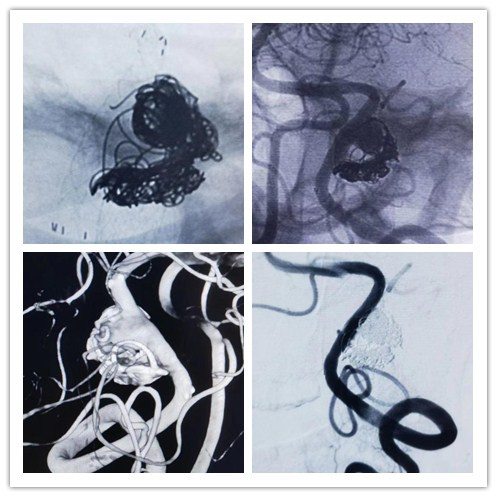

50岁患者杨某某,因自发性蛛网膜下腔出血于2022年6月就诊于兰大二院神经外科三病区。经脑动脉造影术检查后,发现患者左侧椎动脉颅内段夹层动脉瘤,结合病情建议使用密网支架+弹簧圈治疗。但由于费用比较高,且属于自费项目,患者最终选择普通方式行手术治疗。手术顺利,患者非常满意。

2023年4月,该患者前来常规复查,经脑动脉造影术后,发现左侧椎动脉夹层动脉瘤复发,情况紧急,若不及时治疗,将会再次引起颅内出血。此次医生仍建议患者行密网支架+弹簧圈治疗,但患者家庭情况非常困难,一时难以下定决心。就在此时,神外三病区任军主任和周保元主治医师得知有密网支架免费扶持项目,虽然该项目在全国只有约100人的名额,难度很大,但经过他们的多方努力和积极争取,终于成功获得1个免费扶持名额,也是该项目在甘肃省第一个免费扶持名额。手术十分顺利,术后患者恢复良好,于今日出院。